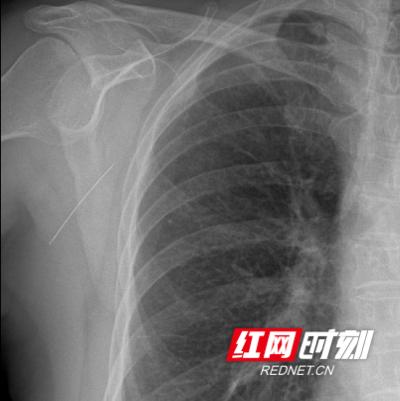

无奈之下,李大妈只得住进颈胸外科,科副主任接诊后对李大妈详细做了体查,针是斜插进背部的,体表已摸不到针的轮廓,而且由于针尖很锋利,肩膀又经常活动,目前针已离开入口向前方移动了2厘米。为避免针继续向前移动,也担心针向更深处刺进胸腔,必须立即手术取出绣花针。手术的难度在于针很细,操作过程仍有向前移动的可能,即使有超声体表定位,也不一定能找到针。最终,副主任制定了“术中超声定位,垂直体表定位线切开,原路退针再自切口取出避免二次损伤”的方法,仅用了10分钟就取出了刺入大妈背部的这根针。